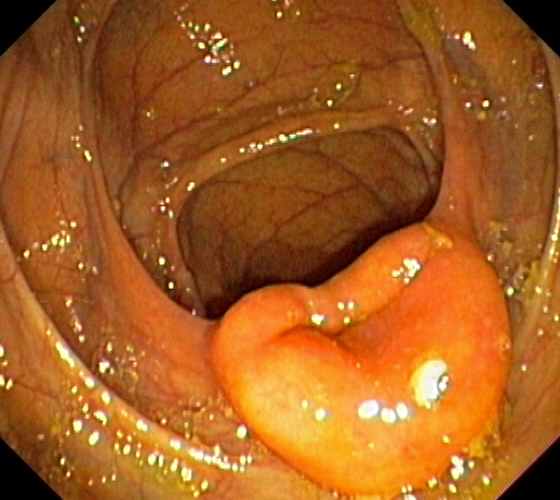

Ileocaecal valve